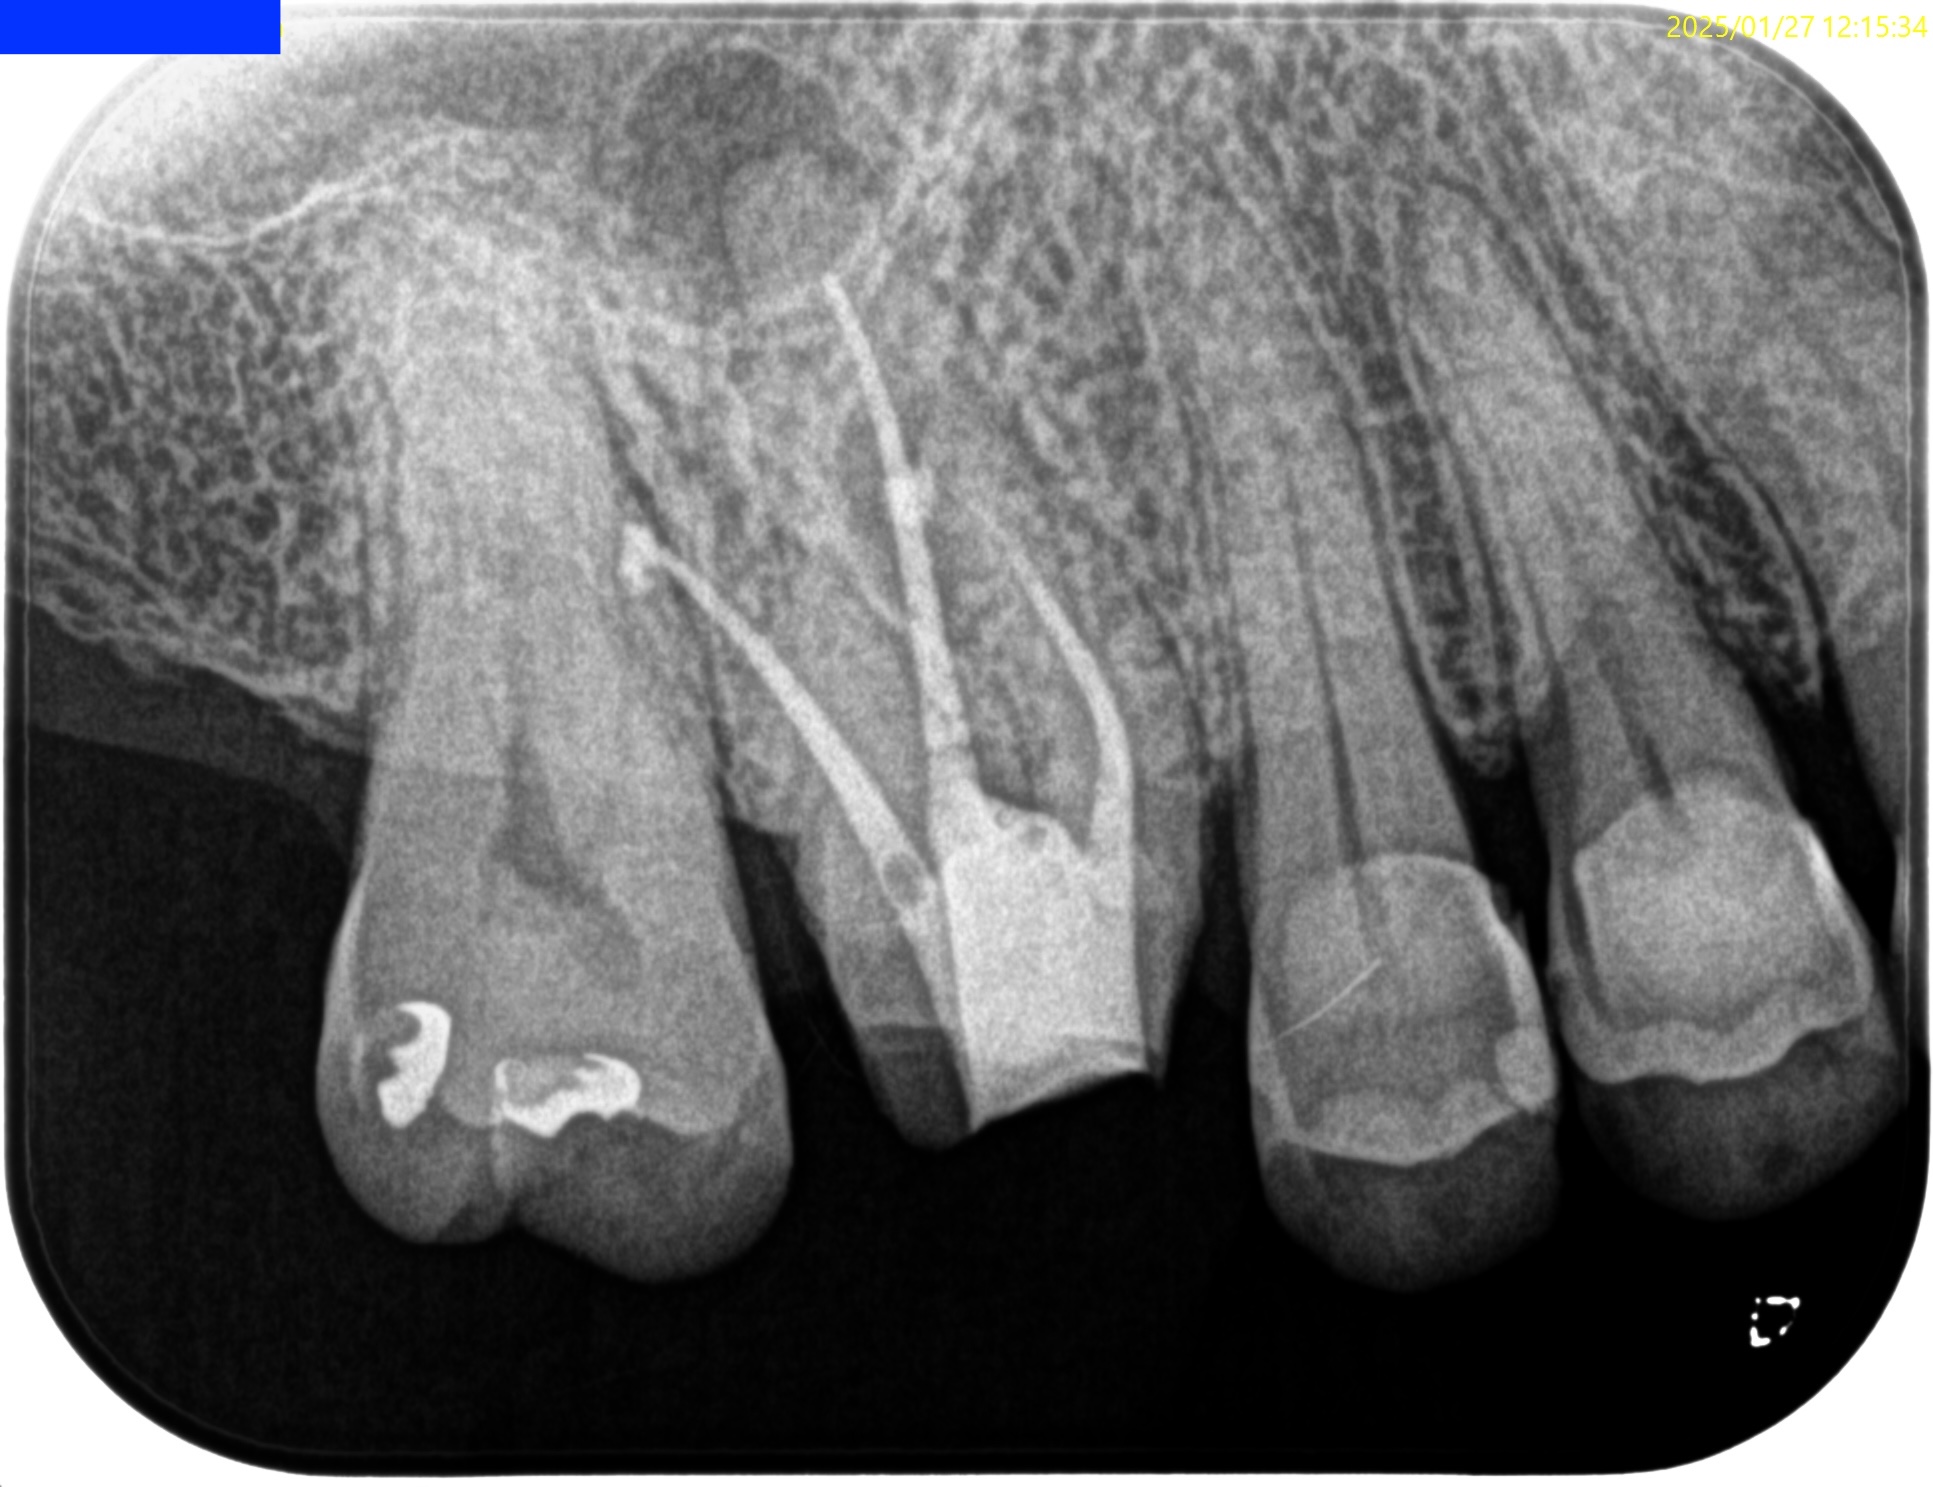

#3 RCT(2025.1.27)

PがUnderextensionの根充のような印象を与える…

が、時間が経過しないと治癒するか否かはわからない。